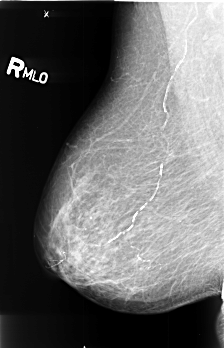

B_3413_1.RIGHT_MLO

RIGHT_MLO LINES 4520 PIXELS_PER_LINE 2912 BITS_PER_PIXEL 12 RESOLUTION 50 NON_OVERLAY